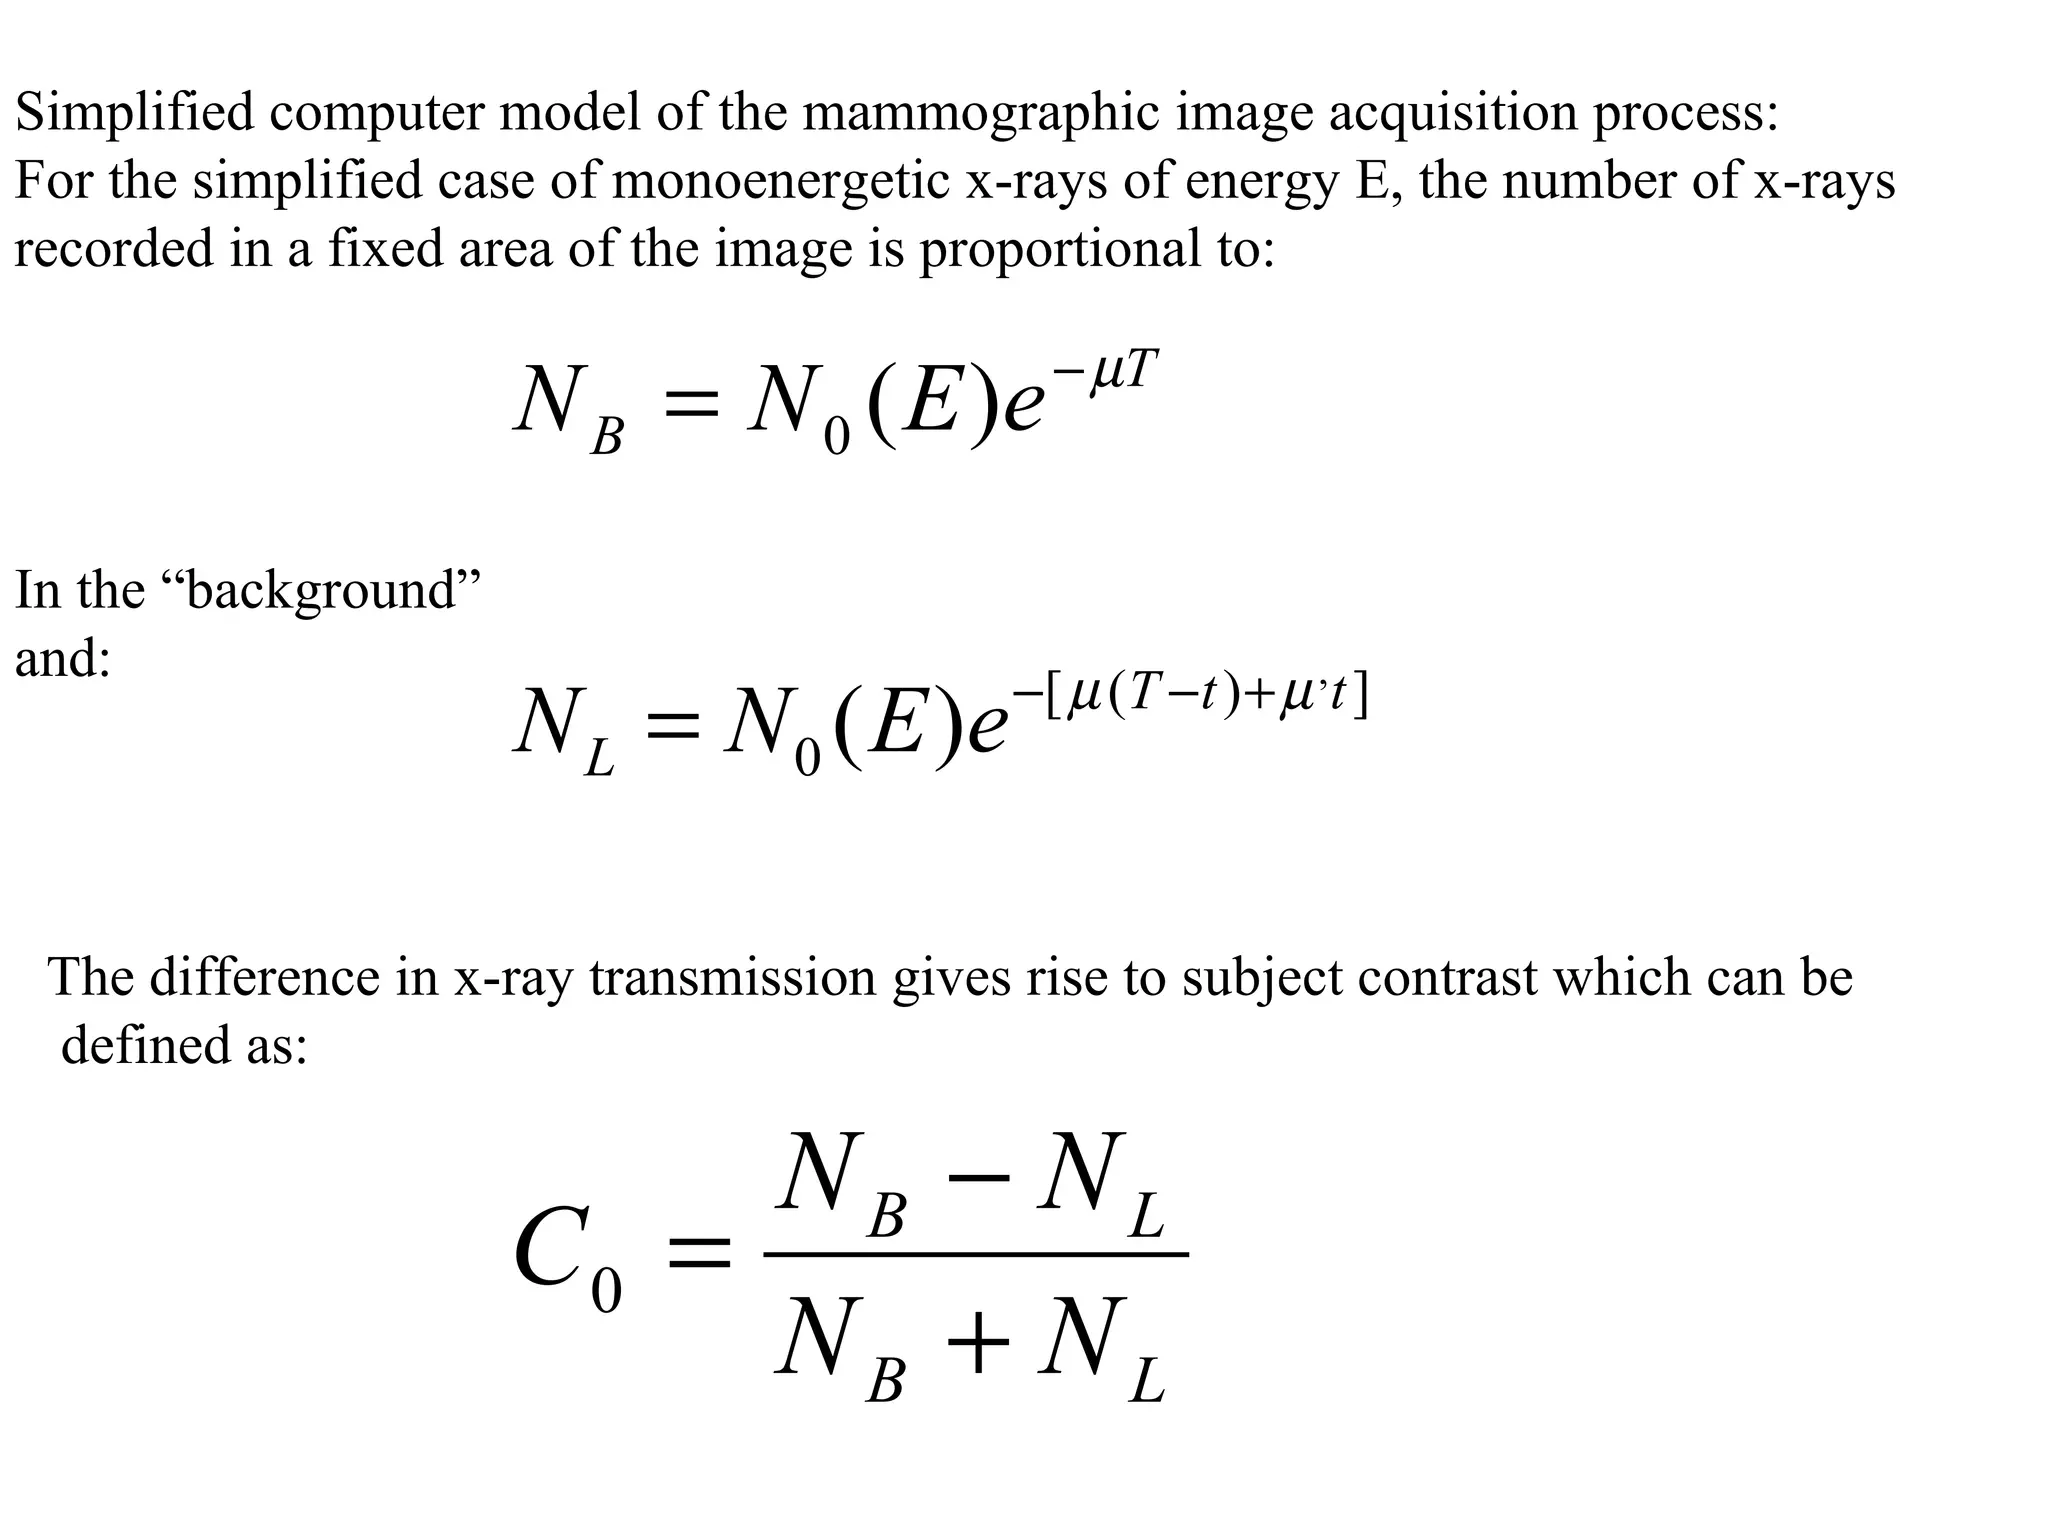

The document discusses various medical imaging modalities including x-rays, computed tomography (CT), and digital mammography. It describes the basic principles and historical development of these technologies, how images are formed, and what types of anatomical features and abnormalities they can detect. Key advances include the development of digital systems that allow image manipulation and remote consultation. While promising, digital mammography still faces challenges around resolution and cost.